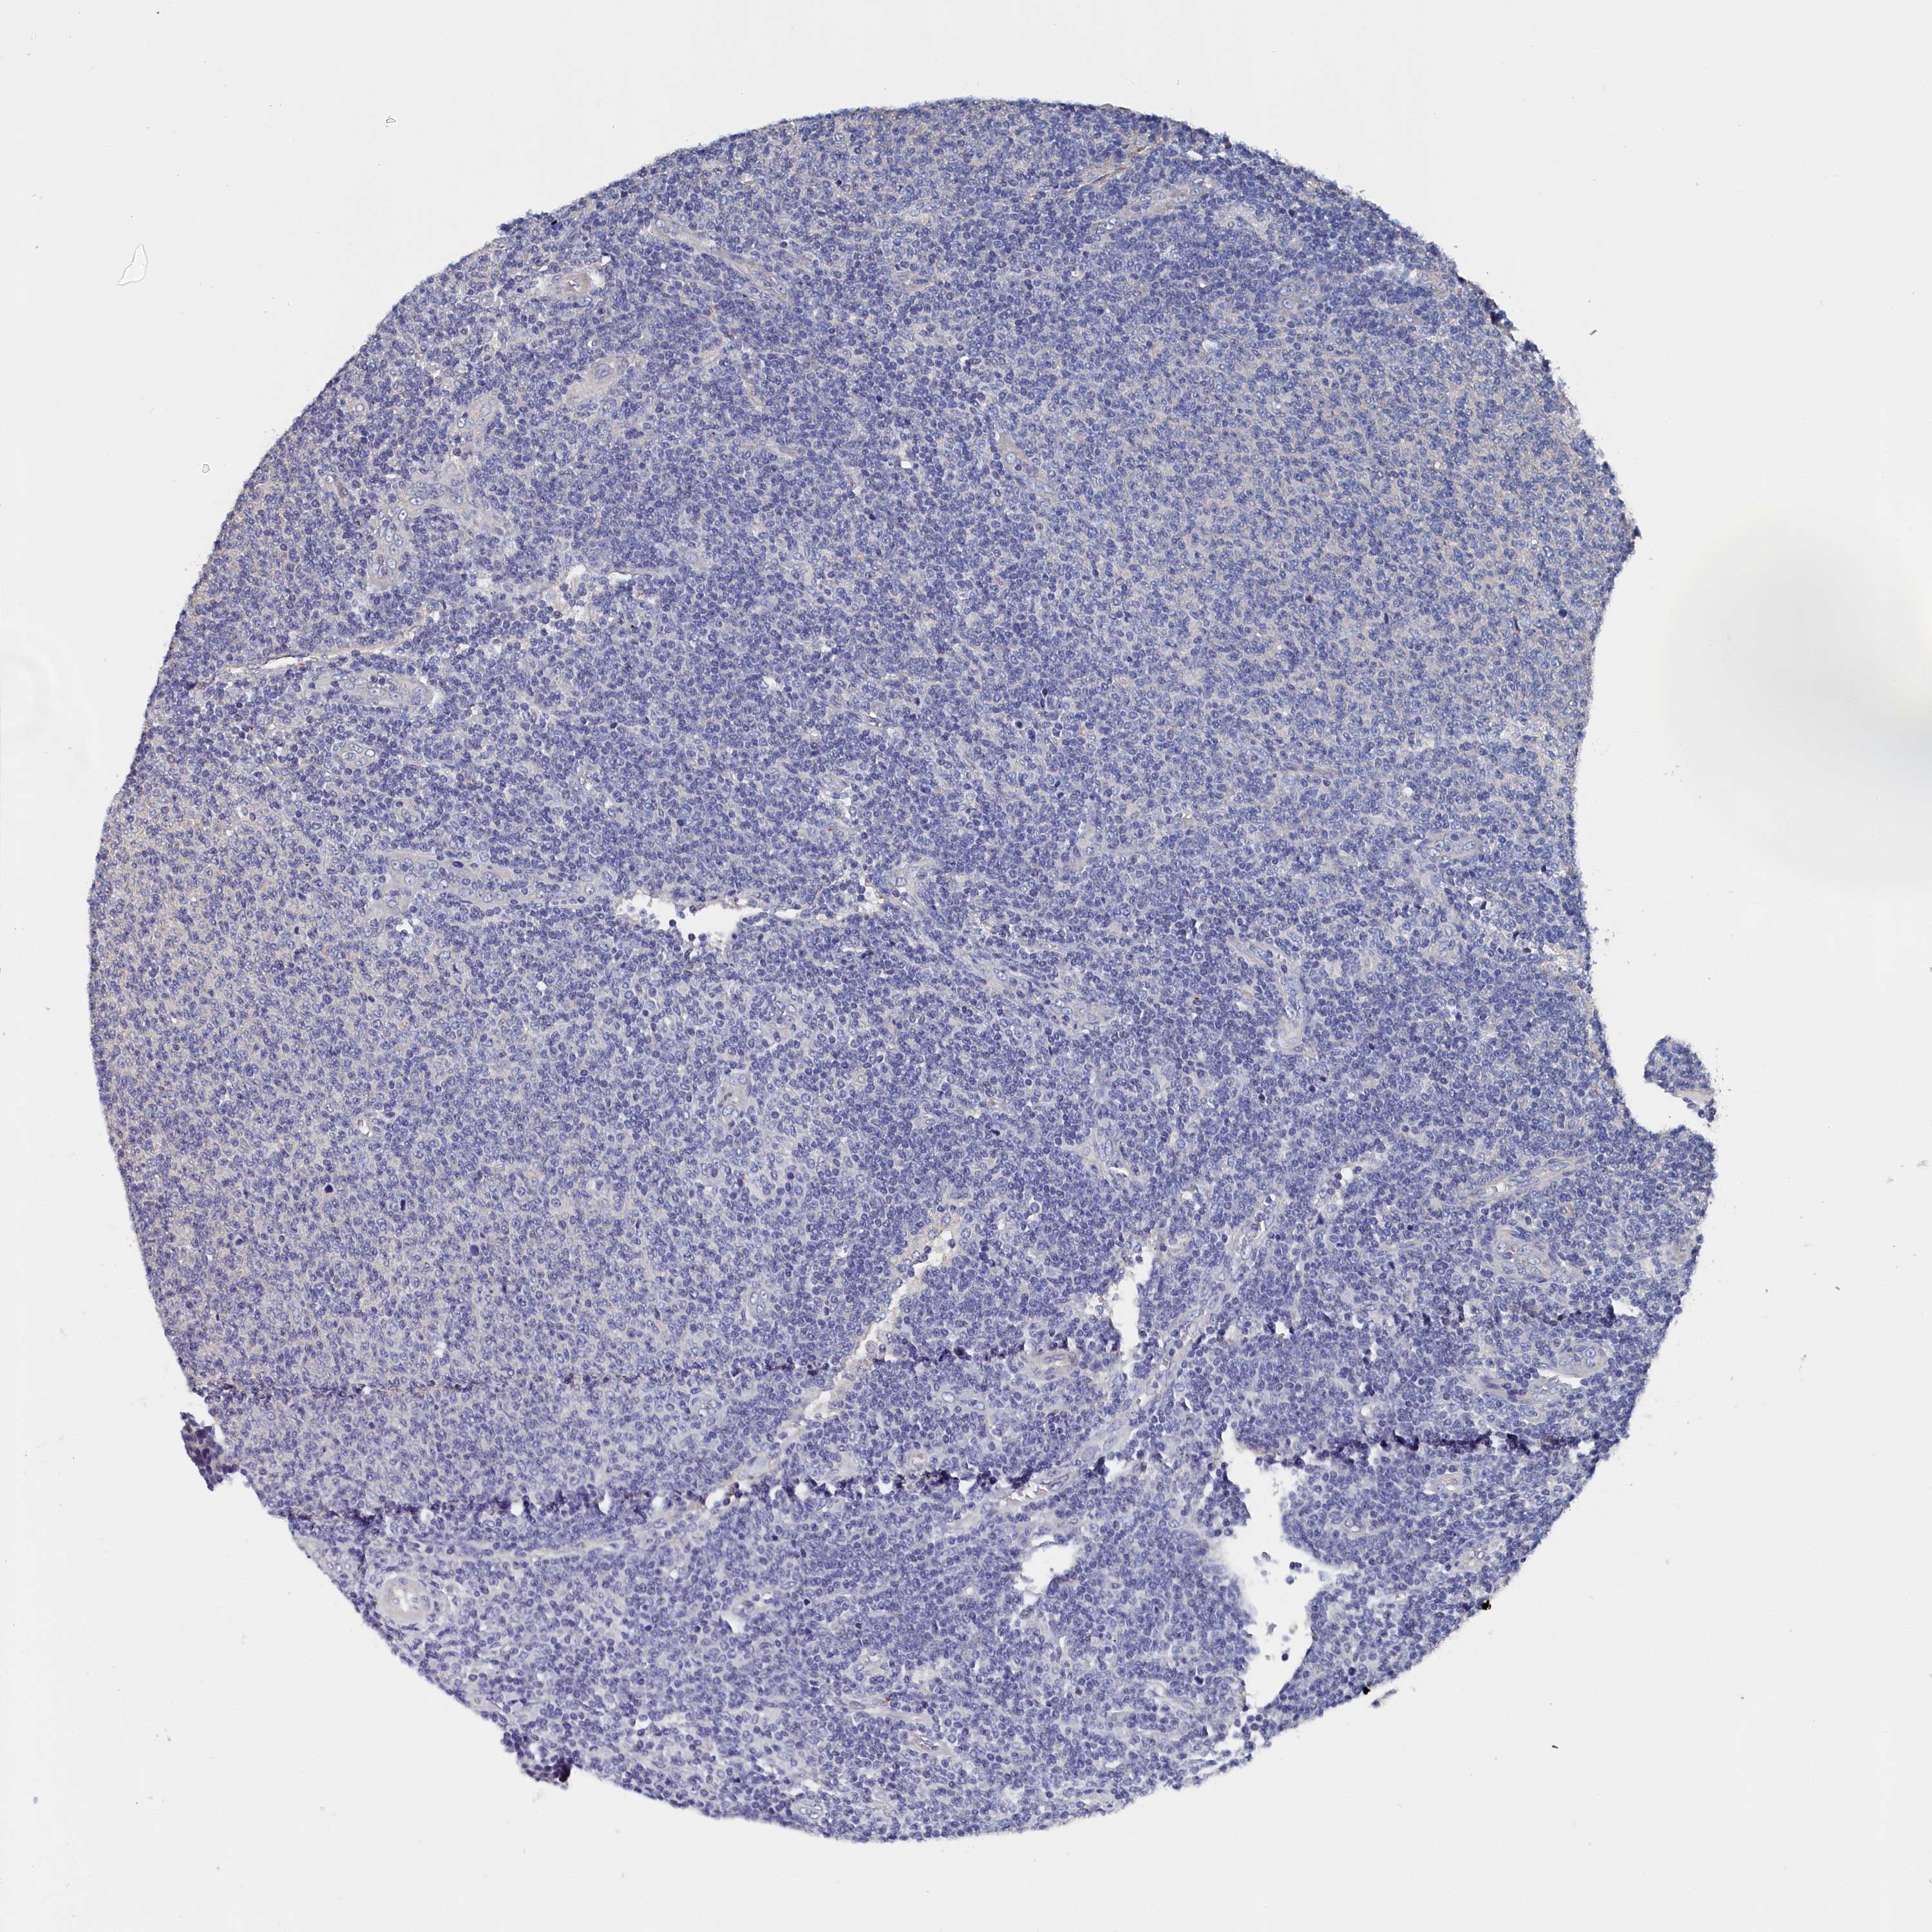

CANCER LYMPHOMA Show tissue menu

Lymphoma

LYMPHOMA - Protein expressioni

A mouse-over function shows sample information and annotation data. Click on an image to view it in a full screen mode. Samples can be filtered based on level of antibody staining by selecting one or several of the following categories: high, medium, low and not detected. The assay and annotation is described here.

Antibody stainingi

Antibody staining in the annotated cell types in the current human tissue is reported as not detected, low, medium, or high, based on conventional immunohistochemistry profiling in selected tissues. This score is based on the combination of the staining intensity and fraction of stained cells.

Each image is clickable and will lead to virtual microscopy that enables deeper exploration of all samples and also displays staining intensity scores, fraction scores and subcellular localization as well as patient and tissue information for each sample.

Antibody HPA038285

Antibody HPA058310

Staining

High

Medium

Low

Not detected

Intensity

Strong

Moderate

Weak

Negative

Quantity

>75%

75%-25%

<25%

None

Location

Nuclear

Cytoplasmic/membranous

Cytoplasmic/membranous,nuclear

Hodgkin's disease, NOS

Malignant lymphoma, non-Hodgkin's type, High grade

Malignant lymphoma, non-Hodgkin's type, Low grade